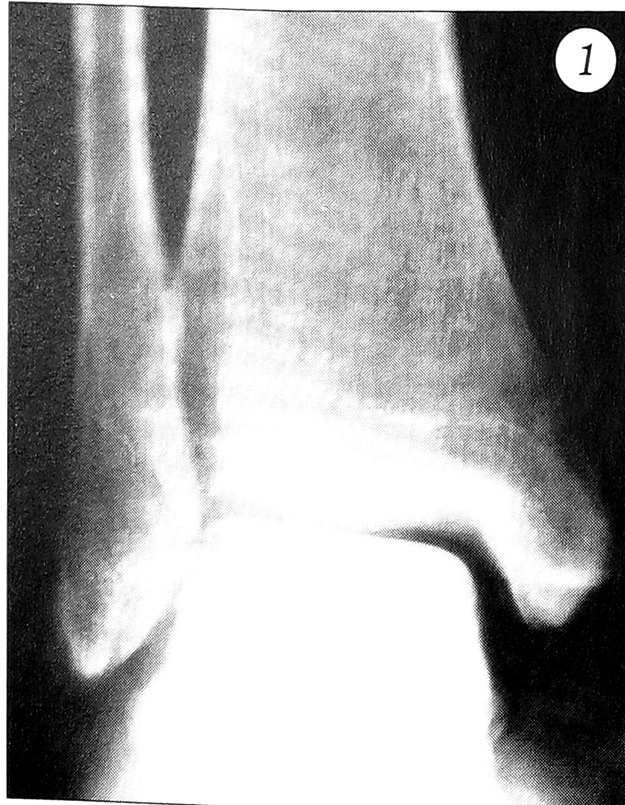

Наши дальнейшие наблюдения показали, что ни в одном случае при непрямом (наиболее частом) механизме травмы голеностопного сустава не обходилось без повреждений капсульно-связочного аппарата. С целью топической диагностики пострадавшим в первые часы после травмы проводили УЗИ поврежденного голеностопного сустава (датчик 10 МГц). У 8 больных было выявлено нарушение целости латеральных связок: у 6 — передней малоберцово-таранной, у 2 — передней малоберцово-таранной и пяточно-малоберцовой. К ранним ультрасонографическим признакам повреждения этих структур были отнесены наличие гипоэхогенных участков неправильной формы с четкими границами, расположенных в толще связок, а также ослабление или отсутствие эхосигнала у мест прикрепления связок к кости (рис. 2).

Рис. 2. Эхограммы голеностопных суставов той же больной С.a — интактный левый сустав; б — поврежденный правый: участок гипоэхогенности у места прикрепления латеральных связок к костям стопы.